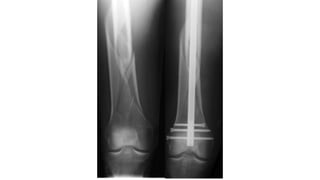

This document discusses femoral fractures, categorized by their location and severity, with classifications such as Garden classification. It outlines the types of fractures, including valgus impacted, non-displaced, partially displaced, and fully displaced, along with their surgical treatment options. Additionally, it briefly describes distal femur fractures, which occur just above the knee joint.